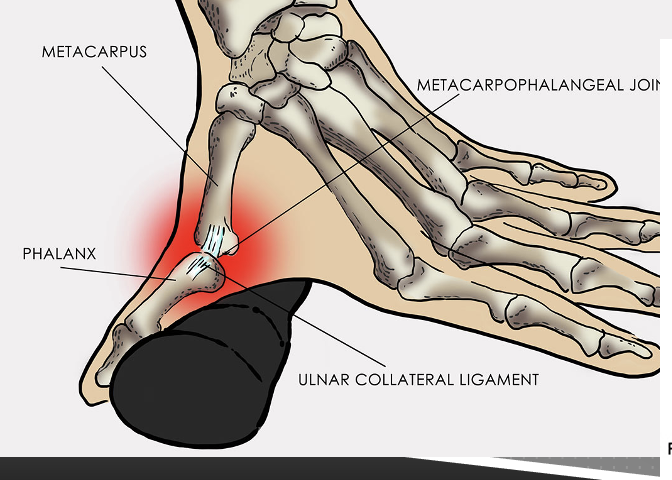

skier’s thumb

ulnar collateral ligament disruption

thumb is forcefully abducted and extended away from hand to where it tears ulnar collateral ligament of thumb at MCP

also known as game keeper’s thumb